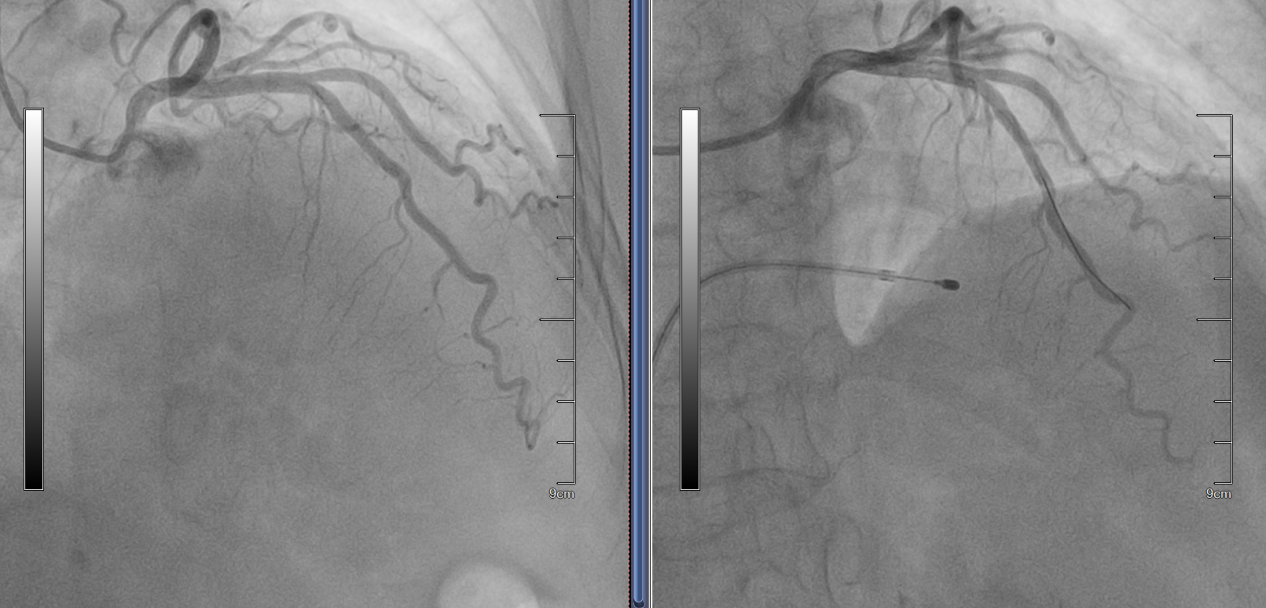

近日,苏州大学附属第四医院心内科周亚峰教授、赵良平主任团队成功完成了我院第一例“经皮室间隔心肌消融术(PTSMA)+经皮腔内室间隔支微粒球栓塞术”,为一名重症梗阻性肥厚型心肌病患者解除生命威胁。

苏大附四院心内科周亚峰教授团队对患者进行了全面评估,确诊其为梗阻性肥厚型心肌病。在优化药物治疗无效后,团队决定采用PTSMA手术进行治疗。手术过程中测量显示患者左心室与主动脉根部压力阶差高达88mmHg,具备明确的介入治疗指征。术中,手术团队通过导管将药物及微粒球精准注入心脏冠脉间隔支血管,选择性消融异常增生的心肌组织,从而减轻左心室流出道的梗阻。术后,患者压力阶差降至10mmHg,胸闷症状显著改善,顺利康复出院。